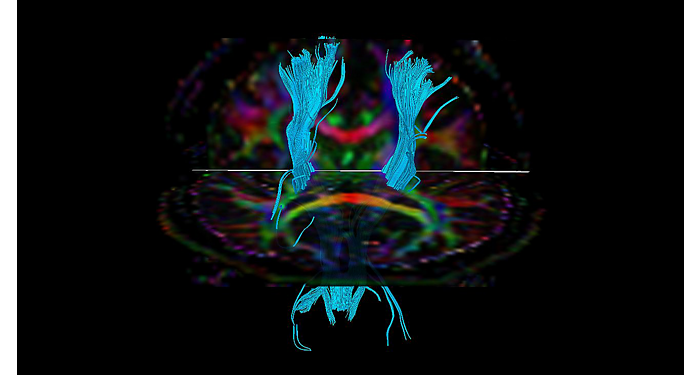

70% of radiologists consider neuro indications to be challenging, mostly due to a lack of appropriate imaging and visualization techniques¹. Philips aims to provide the best possible diagnostic clarity and treatment guidance for all patients with neurological disorders. By leveraging our dStream digital platform, this year, we are introducing, a set of novel imaging and visualization strategies. These may empower you to resolve complex neuro questions with more certainty, as well as unlock new neuro territories in advanced Neurofunctional applications. This is a key step towards elevating neuro diagnostics and ultimately touching more lives with MR imaging. ¹ TMTG Market Survey 2016

New neuro applications